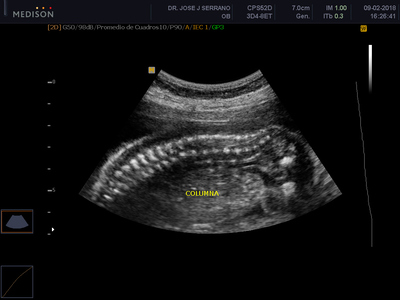

Esta ecografía busca detectar anomalías fetales explorando detalladamente cabeza, cara, tórax, abdomen, genitales y extremidades, así como todos los órganos del bebe (cerebro, corazón, pulmones, riñones, etc). También se tomarán las medidas fetales para compararlas con el tiempo de embarazo y descartar problemas de desarrollo y crecimiento. Además, se evaluarán los movimientos del feto, su patrón de respiración, tono fetal, flujo sanguíneo, entre otros.